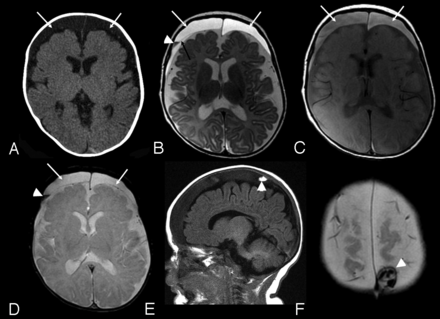

The SDC were identified initially on CT in 2 cases and on MRI in 4 (On-line Table). All SDC cases were referred because of macrocrania. Both CT cases had MRI within 9 days, which confirmed the CT findings. SDC were bilateral in 2 cases and unilateral in 4, localized over the convexities, with a mean size of 5.4 mm (range, 1–9.6 mm). In 4 cases (cases 2, 3, 5, and 6), the SDC were homogeneous, unilateral, and small in size, with similar features on MRI (Fig 1). None of these subjects had recent (within 2 weeks) CT imaging for review. In 2 cases, the SDC were larger, bilateral, and complex in appearance. In case 4, there were heterogeneous signal changes on MRI and increased attenuation on CT, which suggests recent hemorrhage with identified membranes within the collections (Fig 2). In case 1, there was heterogeneous internal signal with visible membranes and different signal intensity components. No CT or gradient-echo evidence of acute hemorrhage was identified.

Case 4. A, Axial CT image. B, Axial FSE T2-weighted image. C, Axial proton density–weighted image. D, Axial gradient recalled-echo image. E, Sagittal T1-weighted image. F, Axial gradient-echo image: 3-month-old boy with macrocrania. Initial CT examination (A) demonstrates moderate sized bilateral subdural collections (arrows), slightly hyperattenuated relative to CSF. MRI examination was performed 14 hours later. Bilateral subdural collections are again identified (white arrows, B, C, and D) hyperintense to CSF on both T2 and proton density–weighted images (B and C). A thin septation is identified on the right (black arrow, B). A layering region of decreased T2 signal is seen on the right (arrowhead, B), which was hyperintense to CSF on T1-weighting (not shown) and blooms on the gradient-echo sequence (arrowhead, D) compatible with blood products. A localized area of increased signal on T1-weighted images in the right parietal vertex subdural collection was noted (arrowhead, E), which was hyperattenuated to brain on CT (not shown) and exhibited blooming on the gradient-echo sequence (arrowhead, F) consistent with additional blood products.